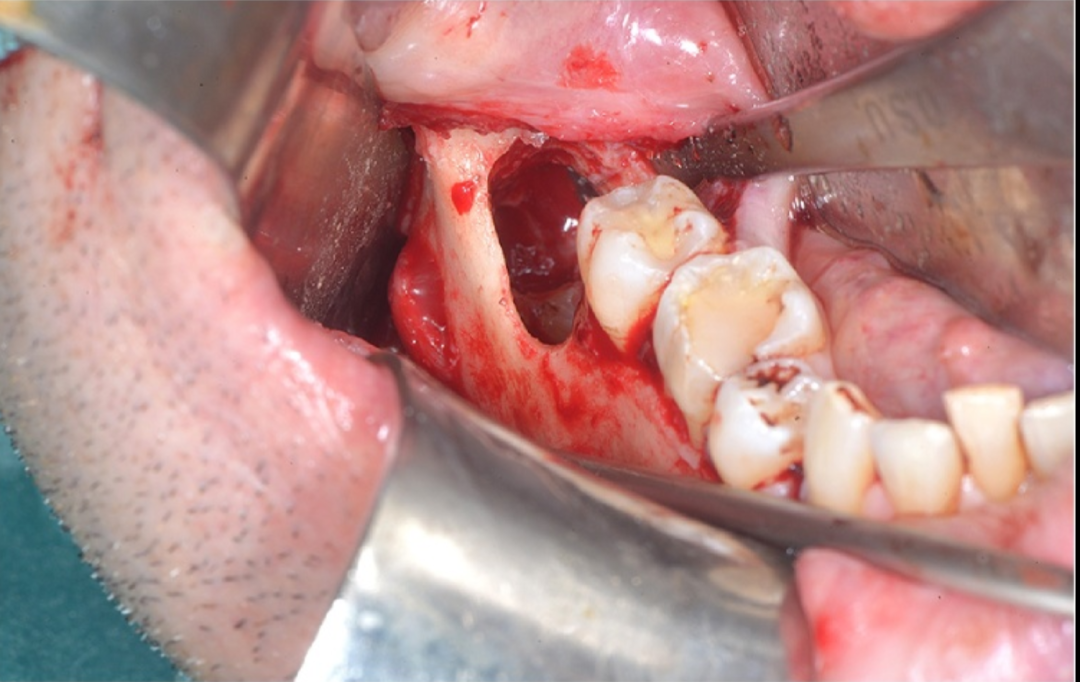

图3 骨板及位于颊侧的下牙槽神经(尚未分离)

在手术中进行翻瓣以暴露第三磨牙时,遇到了一些阻力。经过仔细检查,发现一根与骨膜瓣粘连的绳索状结构。将其轻轻分离后,确认该结构为下牙槽神经。该神经在距离口腔皮质骨外侧1.5厘米处穿出,且没有骨组织覆盖,随后重新进入下颌骨。